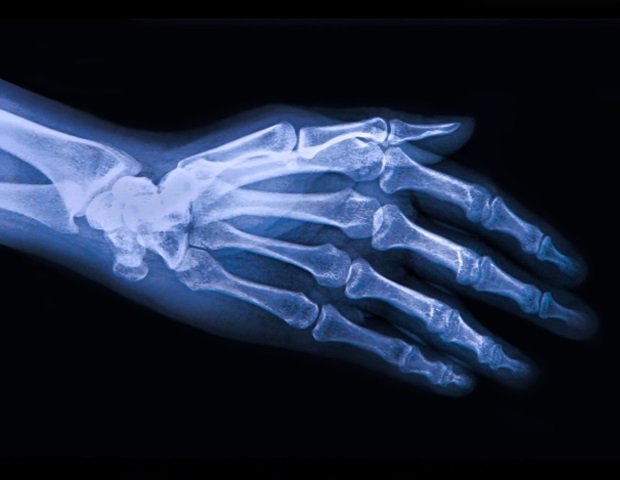

Wanke brings personal experience to this study, having previously performed as a professional dancer. She is currently examining her former field from a medical perspective. The physical toll of training, rehearsal, and performance is evident, with approximately half of all dancers experiencing at least one work-related injury each year. Common injuries include strains and sprains that affect the legs, ankles, and feet, as well as lower back problems. Many continue to work despite the pain, driven by dedication to their profession. By their late 20s, 25% have already developed osteoarthritis, compared to well below 5% in the general population.